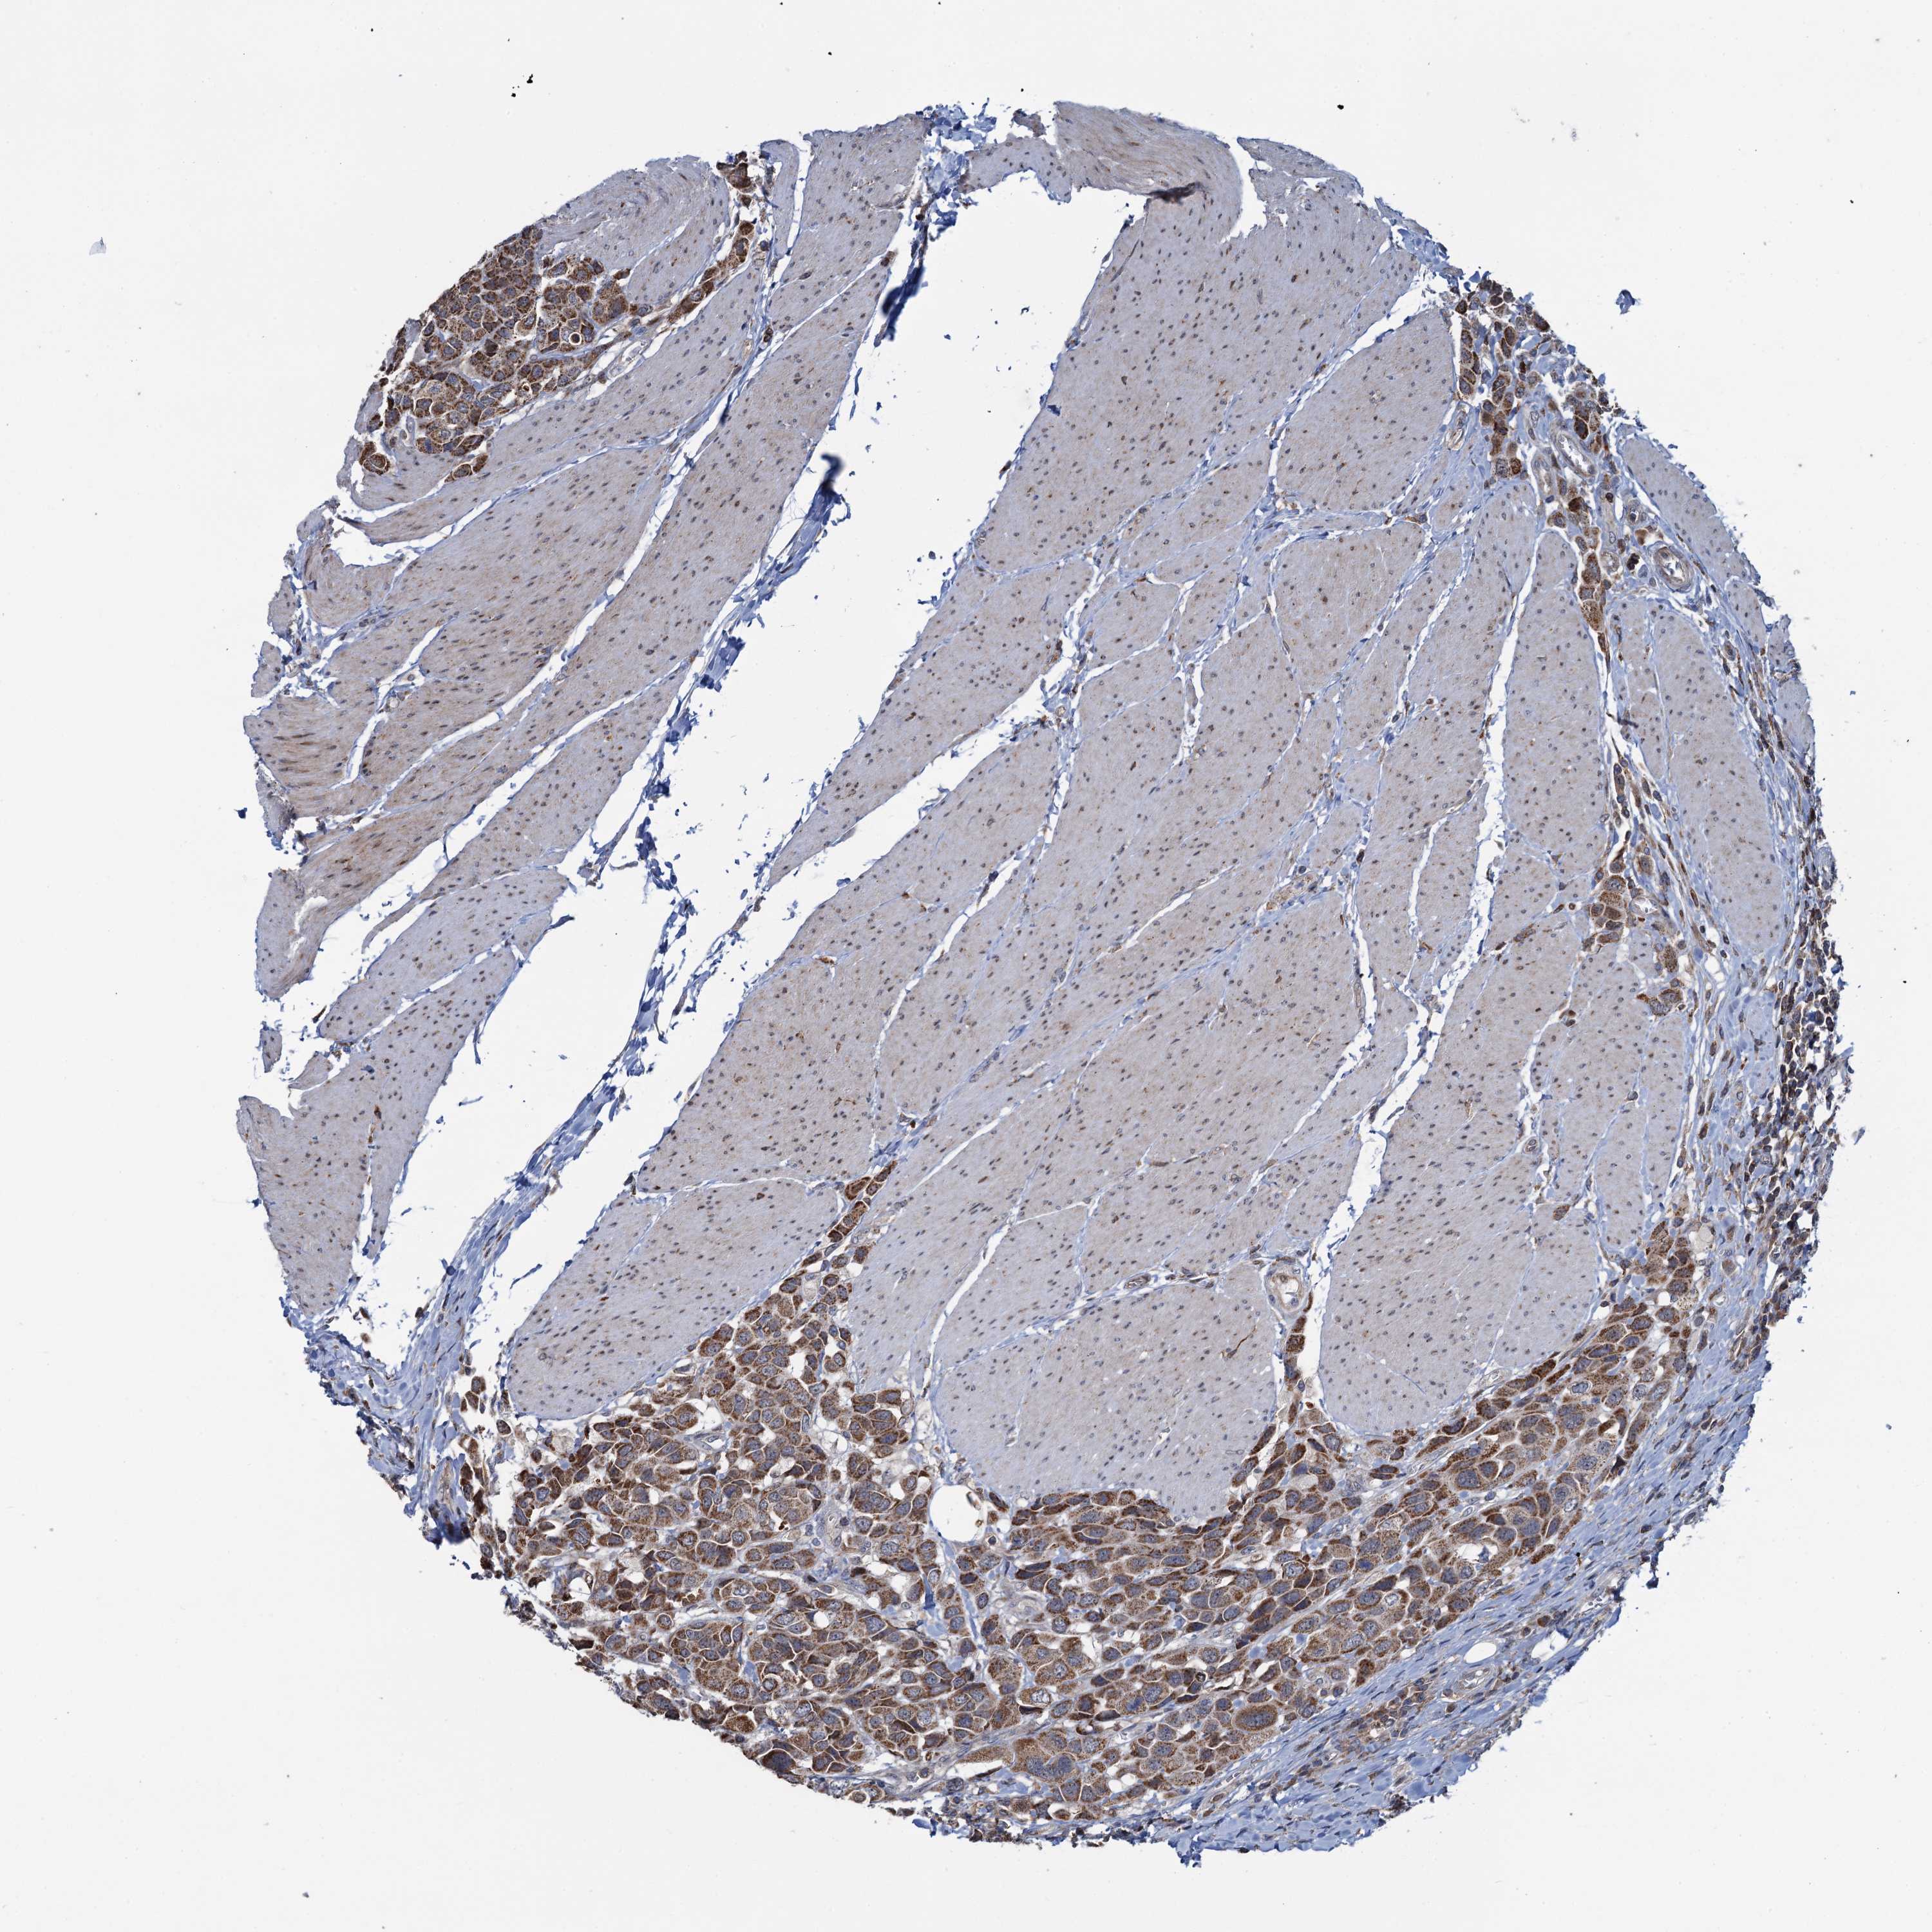

UROTHELIAL CANCER - Protein expressioni

A mouse-over function shows sample information and annotation data. Click on an image to view it in a full screen mode. Samples can be filtered based on level of antibody staining by selecting one or several of the following categories: high, medium, low and not detected. The assay and annotation is described here.

Note that samples used for immunohistochemistry by the Human Protein Atlas do not correspond to samples in the TCGA dataset.

Antibody stainingi

Antibody staining in the annotated cell types in the current human tissue is reported as not detected, low, medium, or high, based on conventional immunohistochemistry profiling in selected tissues. This score is based on the combination of the staining intensity and fraction of stained cells.

Each image is clickable and will lead to virtual microscopy that enables deeper exploration of all samples and also displays staining intensity scores, fraction scores and subcellular localization as well as patient and tissue information for each sample.

Antibody HPA040598

Antibody HPA040958

Urothelial carcinoma, High grade

Urothelial carcinoma, Low grade